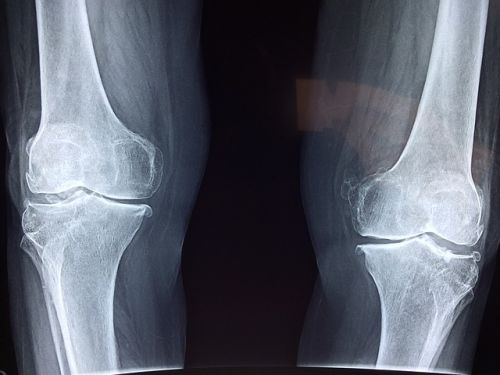

그 외에도 혈액 검사로 요산 농도를 측정하고, X선이나 초음파, CT 등의 영상 검사로 관절 손상과 통풍 결절을 확인할 수 있습니다. 급성 발작 시 혈중 요산 농도가 일시적으로 떨어질 수 있으니, 증상이 없을 때 검사를 반복하는 경우도 있습니다.